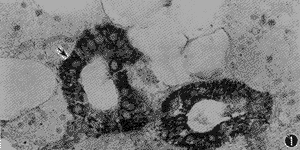

2.腮腺和乳腺癌中3种抗体的表达:2例腮腺组织的分泌管和闰管上皮细胞对3种抗体均呈阳性表达(图1),腺泡细胞则为阴性,肌上皮细胞仅对TGFβ呈弱阳性表达。乳腺浸润性导管癌对3种抗体均呈强阳性表达。阴性对照结果为阴性。

图1 腮腺组织分泌管上皮对EGFR呈强阳性表达(ABC法 ×400)